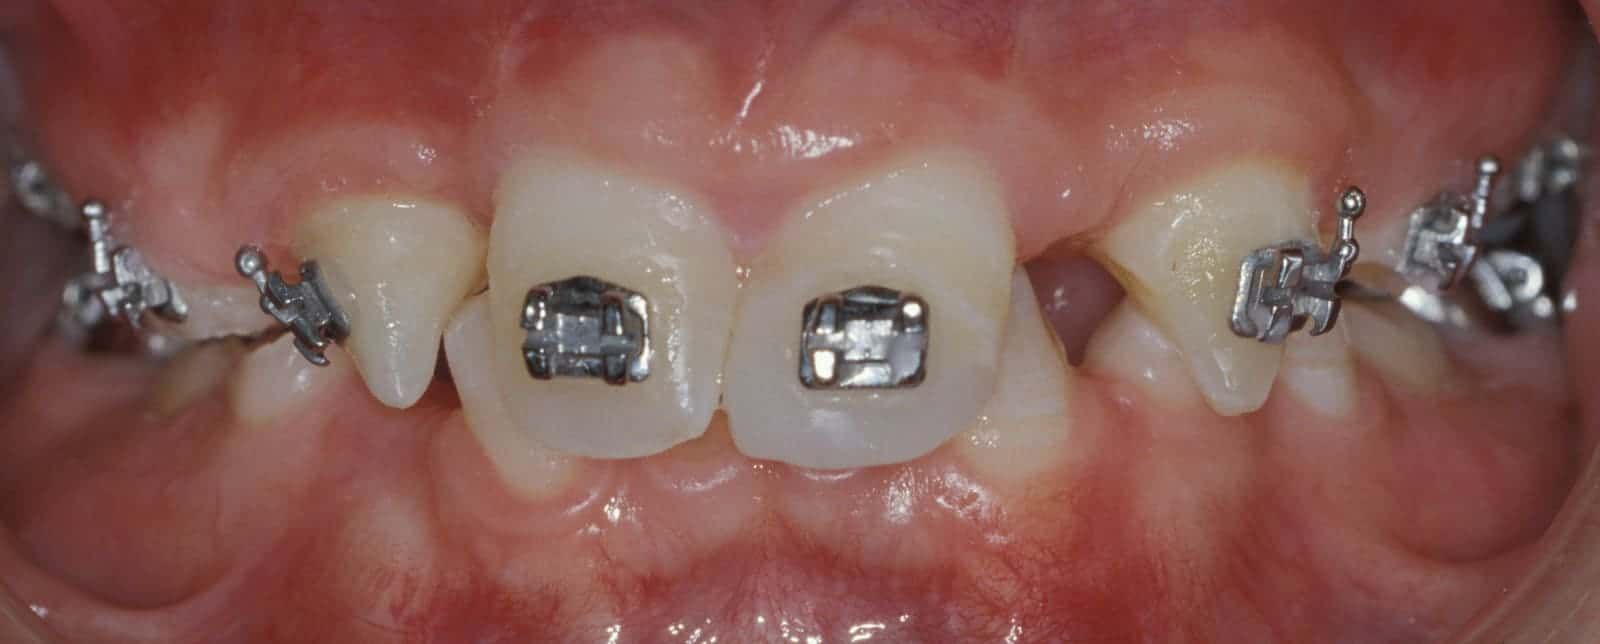

Before: Patient is missing 19 adult teeth. Treatment to replace the missing teeth began at age 12 and was completed at age 21. Treatment involved a team approach, with an Orthodontist, Oral and Maxillofacial Surgeon, and Prosthodontist (Dr. Leopardi) heading the team. Orthodontic therapy was performed first to move existing adult teeth to allow for implant tooth replacement therapy in missing teeth sites (tooth-implant-tooth relationship).